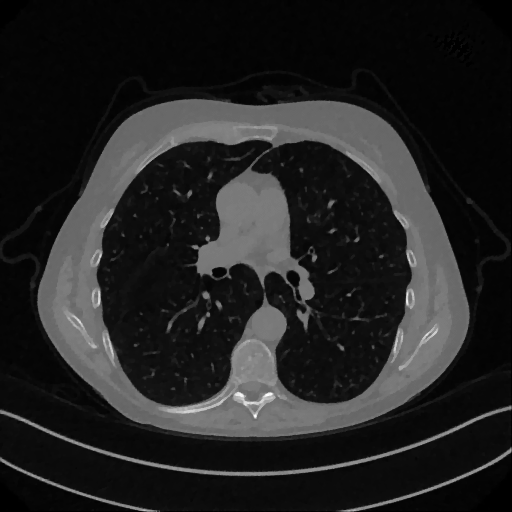

As real patient images, we have downloaded the widely used AAPM Low Dose CT Grand Challenge data set by the Mayo Clinic [35]. The considered images are 512×512512512512\times 512 pixel reconstructions of human abdomen, computed from full-dose acquisitions. In Figure 2 we depict one image with two zooms-in highlighting areas with different anatomical structures, such as pulmonary details, sections of ribs and low-contrast inter-costal muscles. In all the experiments reported in 5.1, we have used the images from the data set as ground truth xGTsubscript𝑥𝐺𝑇x_{GT} references. Coherently, we simulate the tomographic projections of the ground truth images, according to a 2D fan-beam geometry, and we add to the sinograms white Gaussian noise with 102superscript10210^{-2} noise level. To address sparse-view CT reconstructions, we considered two different protocols: the first one is a full angular acquisition with 1-degree spaced projections (we call it P360,360subscript𝑃360360P_{360,360} in the following); in the second one the scanning trajectory covers 180180180 degrees and computed only 606060 projections (it is labelled as P180,60subscript𝑃18060P_{180,60}).

Refer to caption

Figure 2: A ground-truth image from the Low Dose Mayo data set, with two zoomed crops on regions with different anatomical structures.